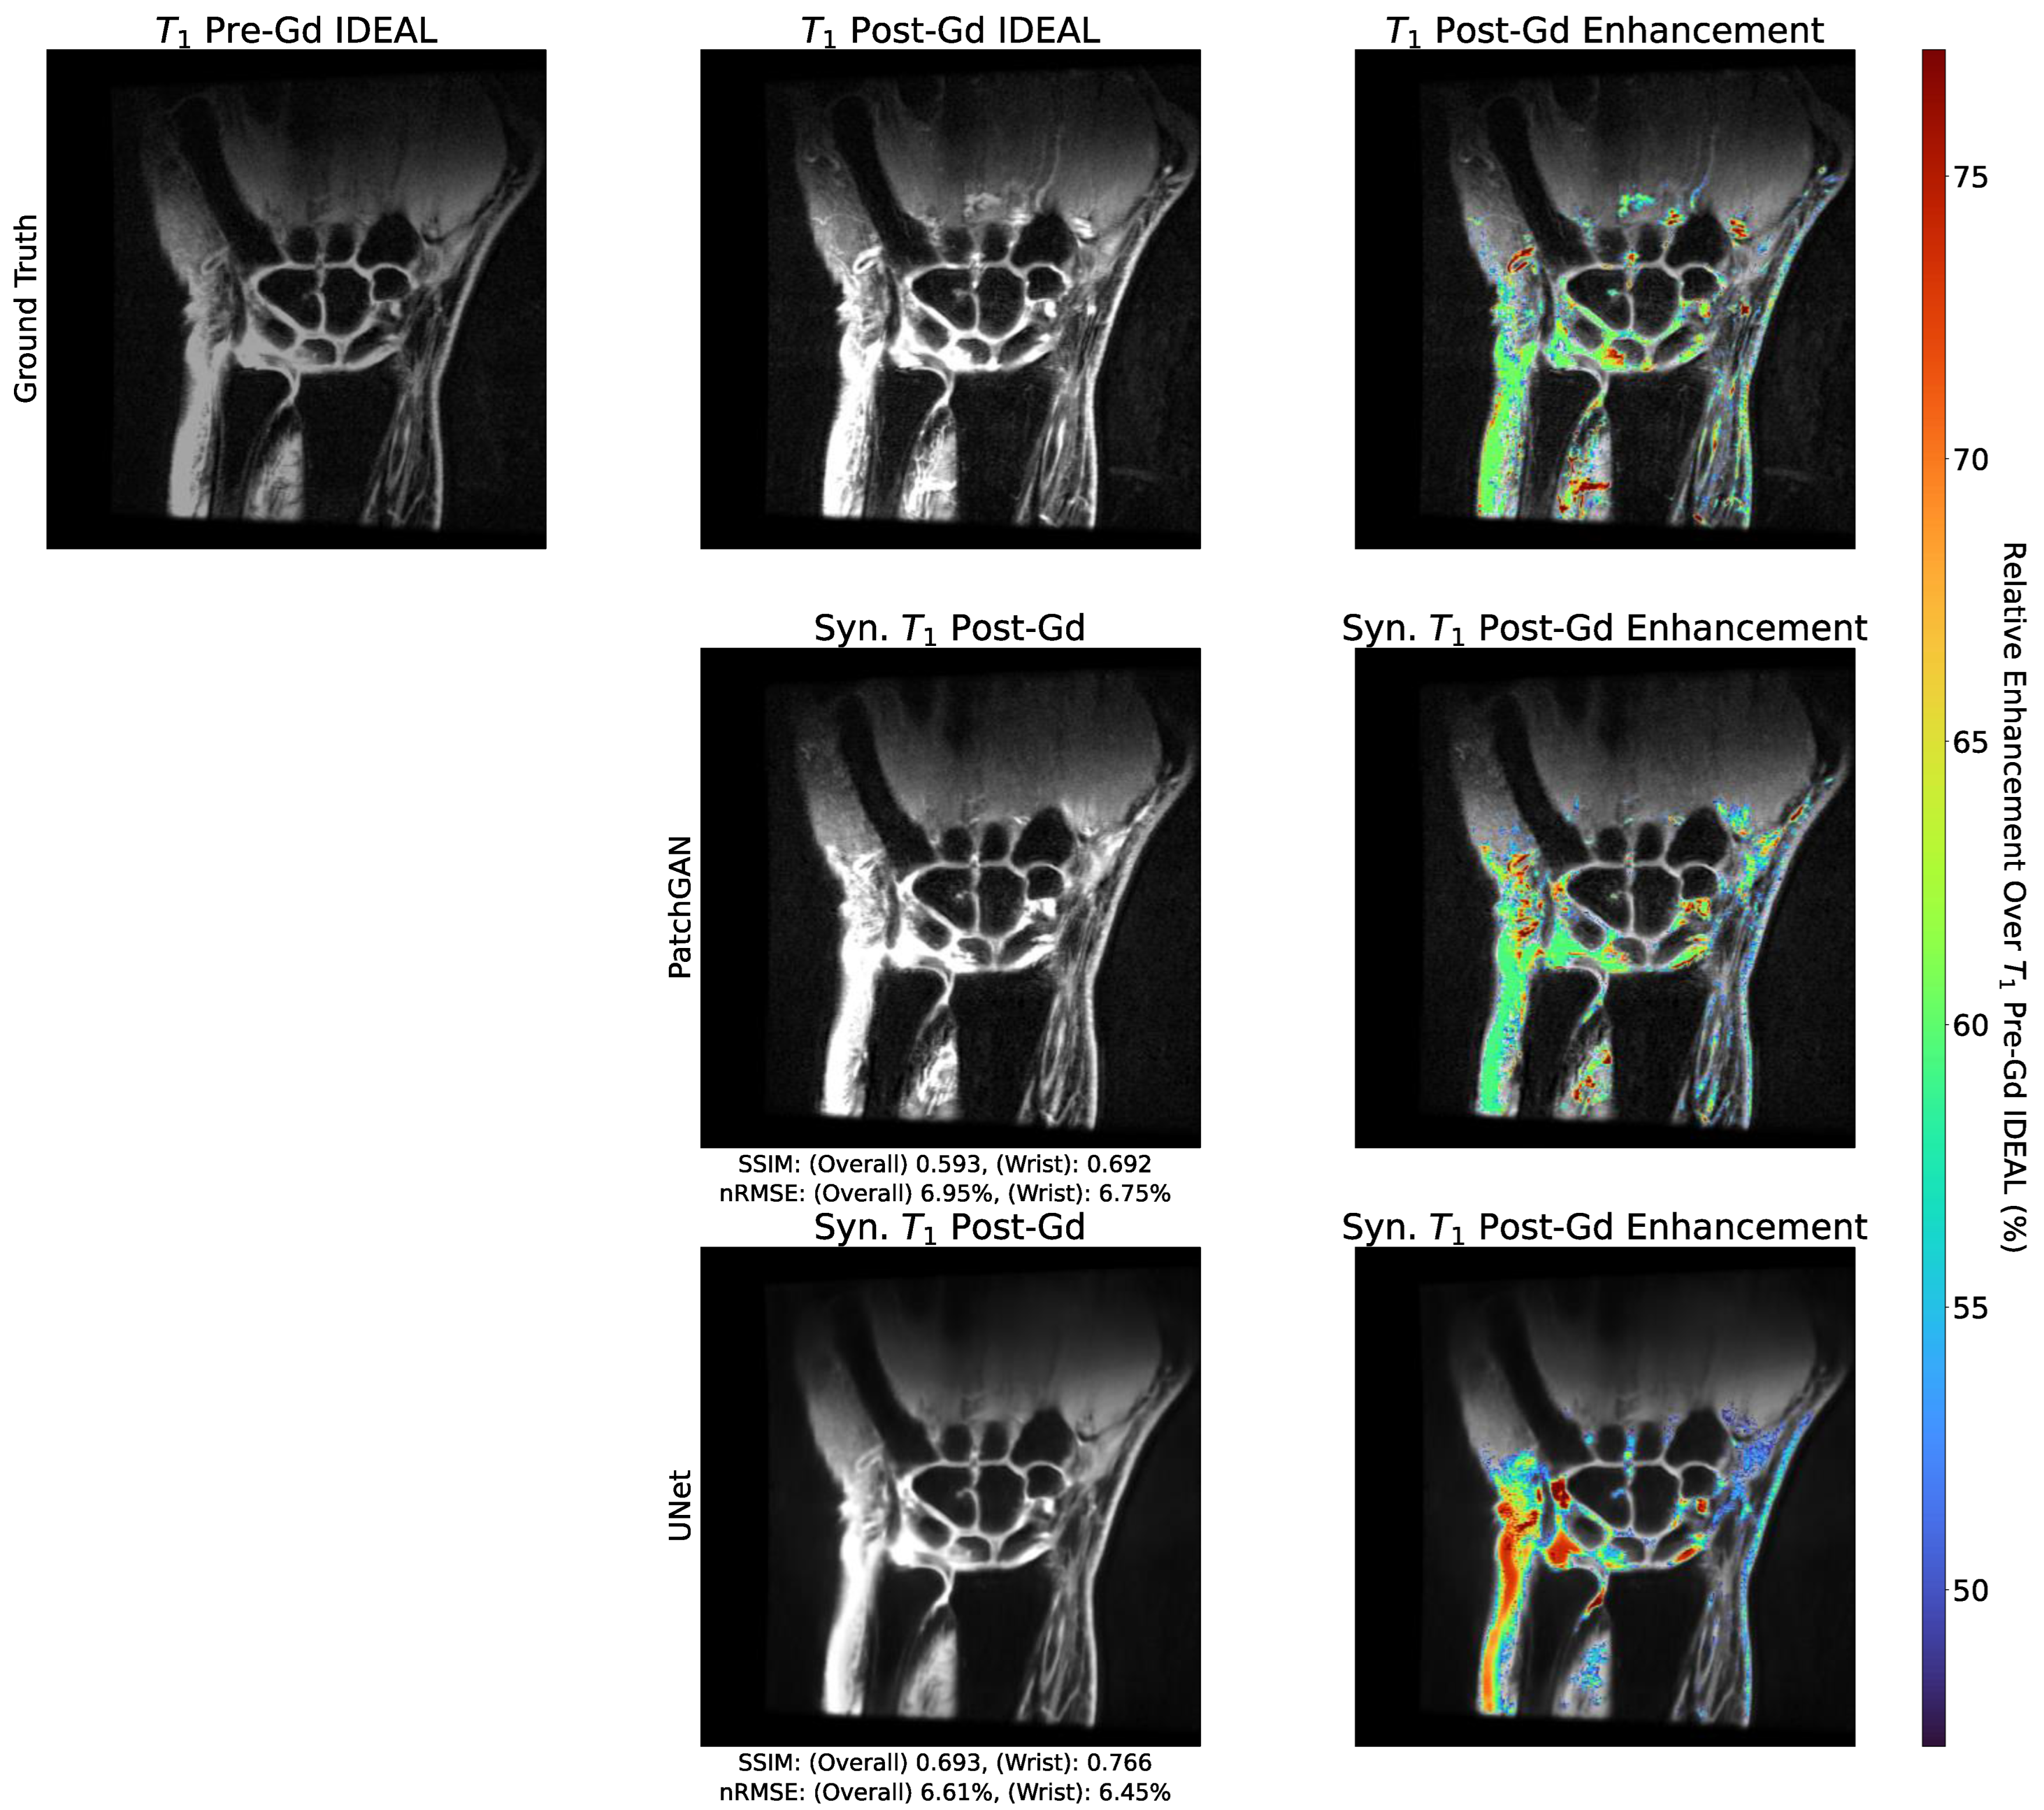

3.5. Enhancement Maps Analysis

3.3. Standard Reconstruction Metrics Performance